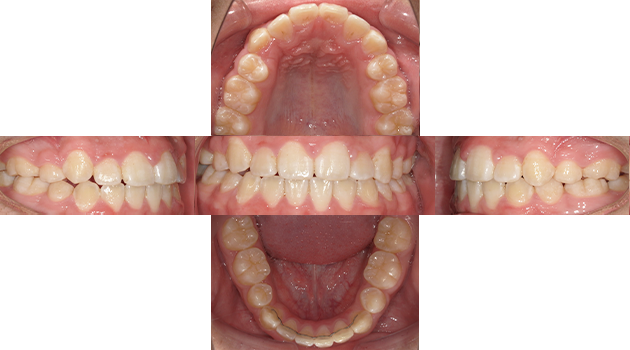

小児矯正と成人矯正

主訴 歯並びを綺麗にしたい。

治療期間 3年

治療費 矯正代金770,000円(税込)

治療内容 小児矯正と成人矯正を行ない健康的な歯並びを手に入れることができた。